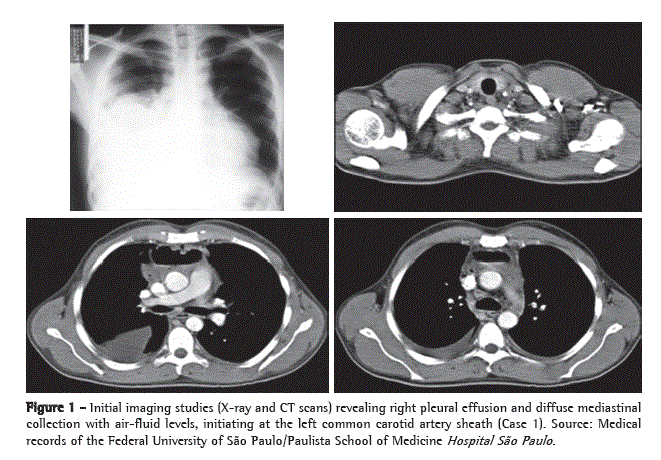

We opted for therapy with broad-spectrum antibiotics (imipenem, cilastatin, and vancomycin) and emergency surgical exploration. The patient was placed in a semi-seated position, with outstretched arms, and his RHT was elevated 30° with the use of cushions. We opted for simple orotracheal intubation. We began with collar cervicotomy at the level of the cricoid cartilage to explore cervical compartments and continued to explore up to the base of the mandible, from where the infectious focus originated. Subsequently, we performed a 1.5-cm thoracotomy incision in the seventh right intercostal space (RIS), introduced a 10-mm fiberoptic bronchoscope (30°), and performed a 6.0-cm accessory anterior minithoracotomy incision in the fourth RIS, through which the entire pleural cavity was cleaned, the mediastinal pleura was opened, and all purulent fluid was drained. We placed an 18 F tube (airtight seal) in the anterior mediastinum and two tubes (water seal) in the pleural cavity-a posterior 18 F tube and an anterolateral 28 F tube. In the cervical region, we placed a Penrose drain, creating communication between the surgical site and the anterosuperior mediastinum, as well between the surgical site and the right pleural cavity, through the pretracheal fascia. Subsequently, the patient was referred to the ICU, where he remained under mechanical ventilation and received low doses of vasoactive drugs. The evolution was favorable, mechanical ventilation and the use of vasoactive drugs were discontinued on postoperative day 2, and the patient was discharged from the ICU on postoperative day 3 (Figure 2). The patient was

discharged from the hospital in good general health on postadmission day 18, without the need for further surgical intervention (Figures 3a and 3b).